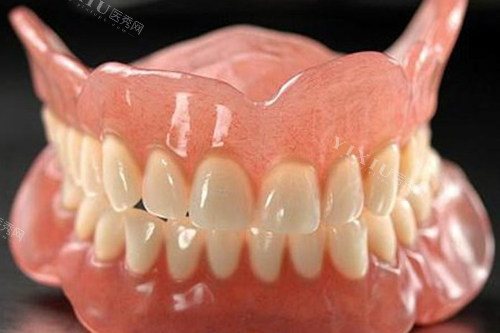

三、活动假牙的特点

活动假牙有以下几个主要特点:

可摘戴:这是它更大的特点,可以随时取下来清洗。

适用范围广:适合多数牙齿缺失的情况,尤其是多颗牙缺失。